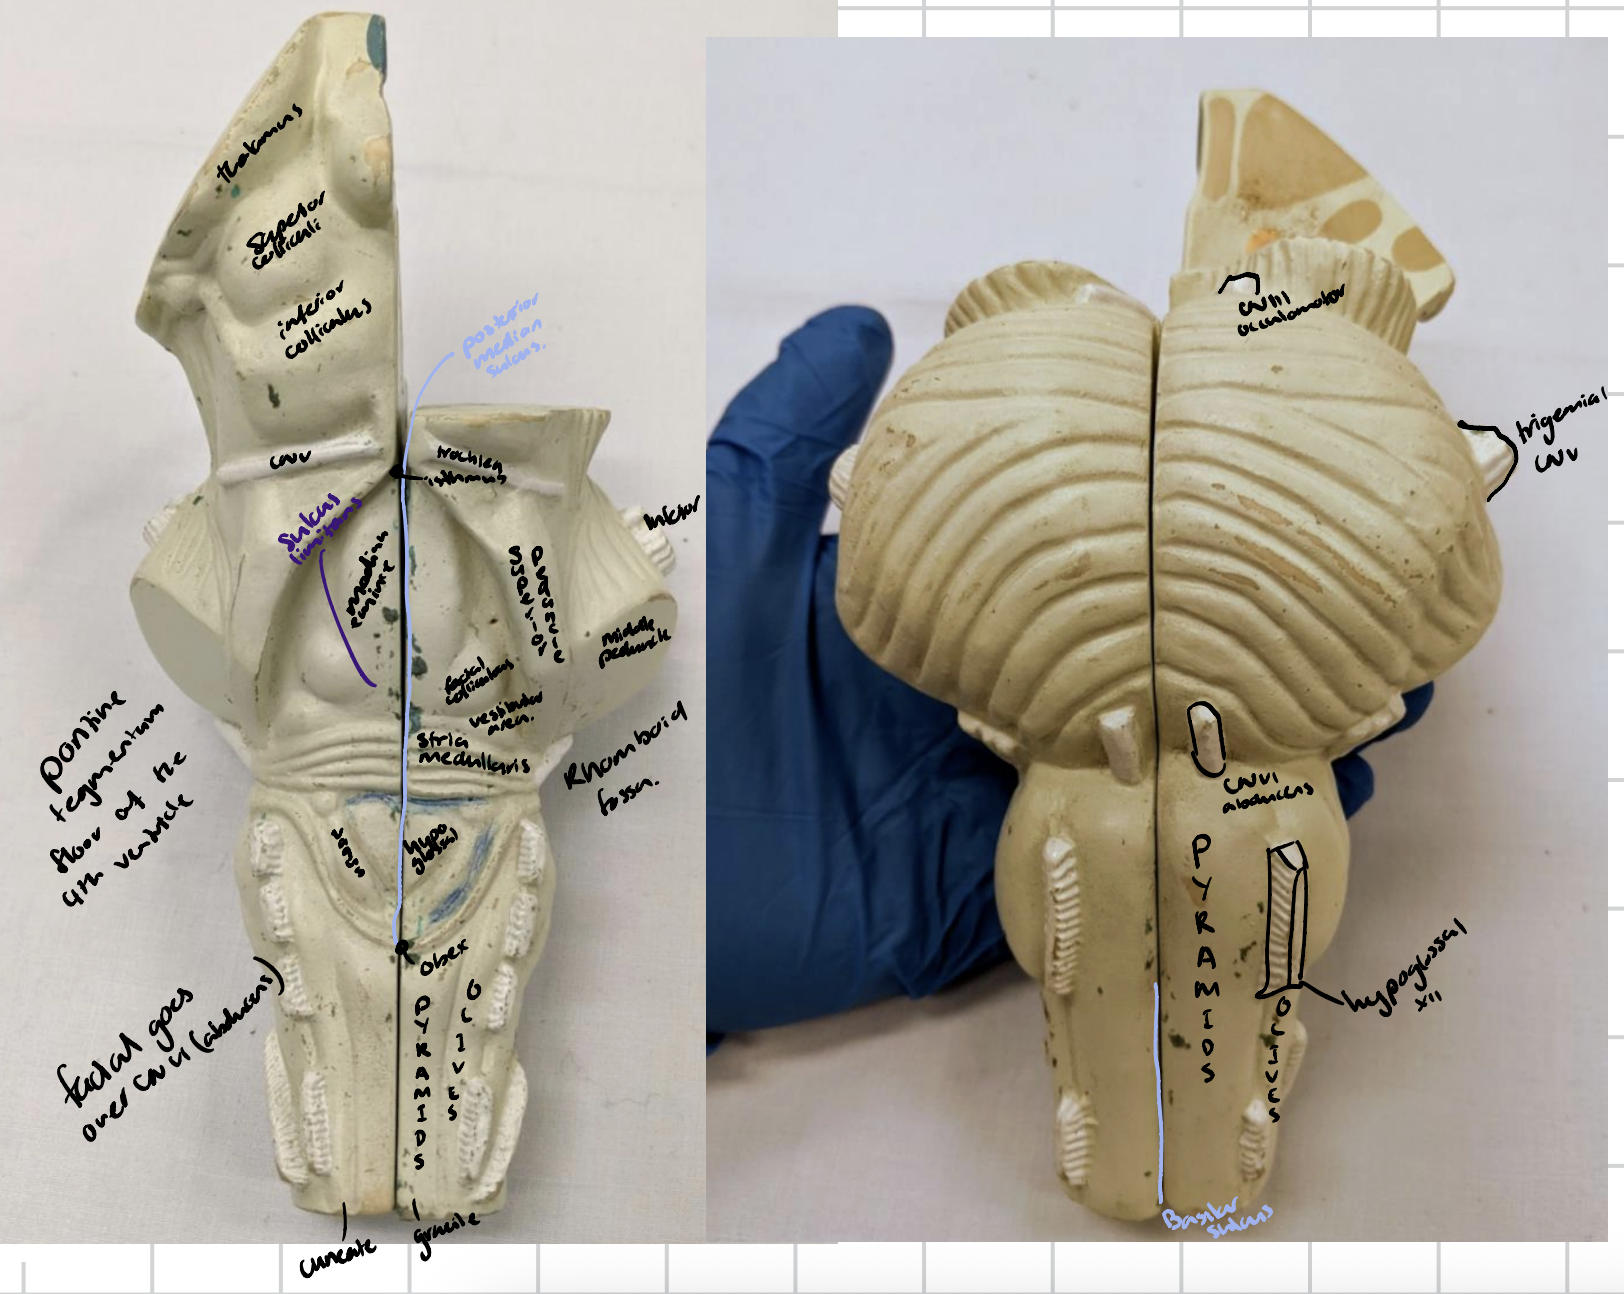

Anterior median fissure

Posterior median sulcus

Orientations of brain

Cerebellum

Anterior lobe of cerebellum

Horizontal fissure

Posterior lobe of cerebellum

Cerebellar tonsils

Posterolateral fissure

Superior medullary velum

Arbor vitae

Folia